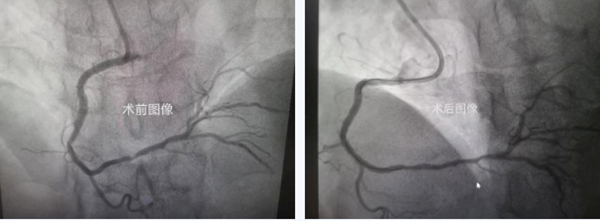

经充分的术前准备工作后,患者接受冠脉造影检查,显示右冠状动脉内支架再狭窄。在多种器械融合操作下,指引导管终于就位,但治疗过程仍困难重重。

虽然导丝顺利通过病变,但因右位心指引导管支撑不足、血管内原支架重度狭窄,导致球囊不能通过狭窄病变。王健主任团队通过多种器械融合掘进技术,逐毫米地将狭窄病变扩张开。输送支架过程更是阻力重重,团队锲而不舍,终于完成了这台罕见病例手术。

右位心患者的冠脉介入治疗

术后,高大叔经过短期心脏康复,已恢复正常的生活和工作状态,露出久违的笑容。